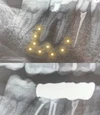

Endodonti